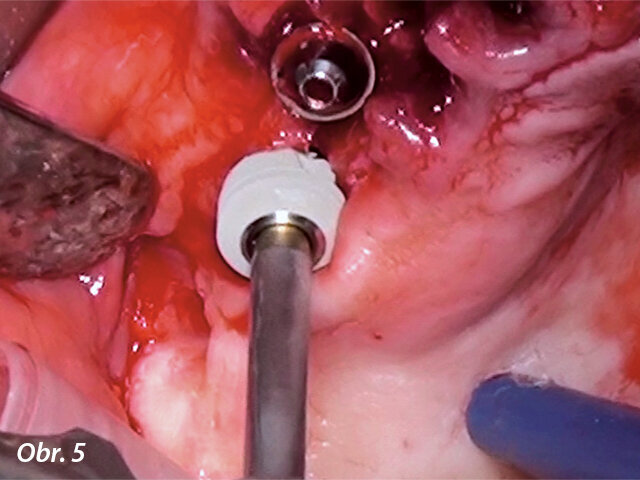

Panoramatický snímek zubů zachycující implantáty v dobré pozici. Ultrakrátké implantáty byly zavedeny v dobrém vztahu k čelistním dutinám, ale byly obklopeny malým množstvím kosti. (fotografie: dr. Ghirlanda)

Panoramatický snímek zubů zachycující implantáty v dobré pozici. Ultrakrátké implantáty byly zavedeny v dobrém vztahu k čelistním dutinám, ale byly obklopeny malým množstvím kosti.

Následně byl odklopen mukoperiostální lalok v rozsahu celého horního oblouku. Byl proveden pečlivý „debridement“, při němž byly odstraněny všechny zánětlivé a fibrózní tkáně a obnaženy všechny kostní defekty. Následně byly pomocí kostních dlátek a kulatých frézek vytvarovány mělké kostní defekty, zatímco hluboké defekty byly vyplněny xenoštěpem (Geistlich Bio-Oss, Geistlich Biomaterials) a překryty vstřebatelnou membránou (Geistlich Bio-Gide, Geistlich Biomaterials). Ve frontálním úseku byly zavedeny standardní implantáty (blueSKY, bredent medical), a zároveň byly v místech prvních molárů umístěny dvě fixtury 5,2 × 6,0 mm (copaSKY, bredent medical) (obr. 5). Z důvodu maximalizace primární stability ultrakrátkých implantátů byla zvolena vnitřní osteotomie k bikortikálnímu ukotvení implantátů. Fixtury nepronikly do sinu, ani nebyla patrná elevace sliznice sinu. Všechny implantáty dosahovaly primární stability ≥ 35 Ncm. Panoramatický RTG snímek pořízený na konci chirurgického zákroku prokázal správné umístění implantátů (obr. 6).